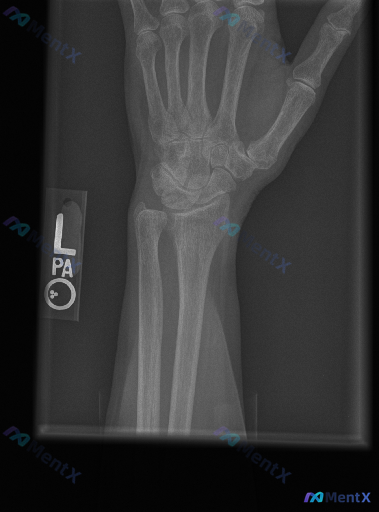

整理到一组左手及腕关节斜位X光片的影像观察资料,想和大家讨论下判读思路与后续临床处理逻辑。 影像观察到的内容 1. 骨骼完整性:舟骨整体轮廓可见,骨皮质连续;头状骨、月骨、三角骨、豌豆骨、钩骨等其他腕骨,以及第1-5掌骨、各指骨骨质连续性均良好,未见明确骨折线、嵌插或骨小梁紊乱表现。 2. 关节对位...